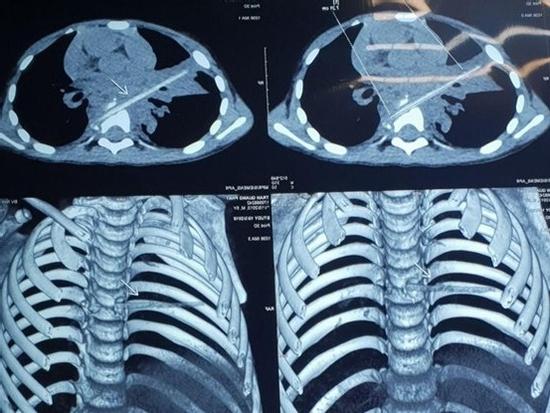

Bé trai bị que xiên thịt đâm xuyên phổi và đốt sống 9 tháng không biết

9 tháng ròng gia đình đưa con trai đi điều trị viêm phổi, tuy nhiên kết quả chụp cắt lớp khiến bác sĩ cũng bất ngờ.